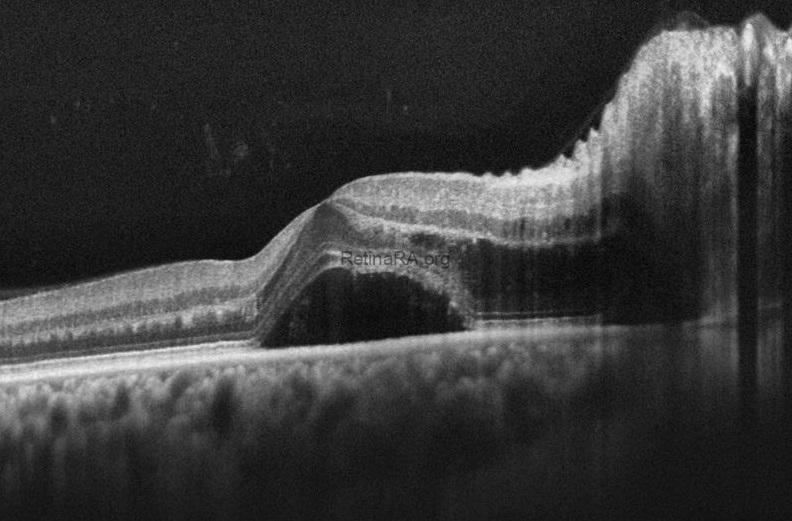

OCT demonstrates serous macular detachment and RNFL edema in the right eye.

Images taken nine days after the start of antihypertensive therapy show that the serous fluid decreased significantly and a half macular star (black arrow) appearance formed.